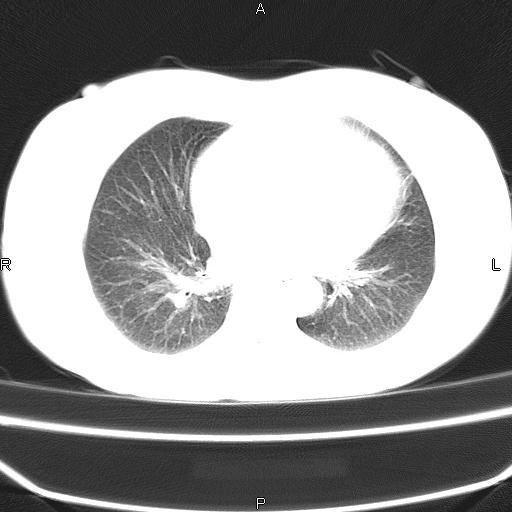

患者,女,66岁。健康体检胸部透视发现右上肺片状阴影。既往无不适,患者自诉三个月前曾有低热病史体温37.5左右一周。用药后缓解。至今无其它不适。请老师们指导指导。

考虑:右肺上叶周围型肺癌(分叶状肿块+砂粒状钙化+胸膜尾征)。

病灶见明显分叶、大小较大(大于3cm?),老年人,多考虑:肺癌,建议穿刺活检。

典型的中心型肺癌,尖段支气管阻塞。

周围性肺癌,

右肺上叶周围型肺癌可能性大。

考虑:右肺上叶周围型肺癌